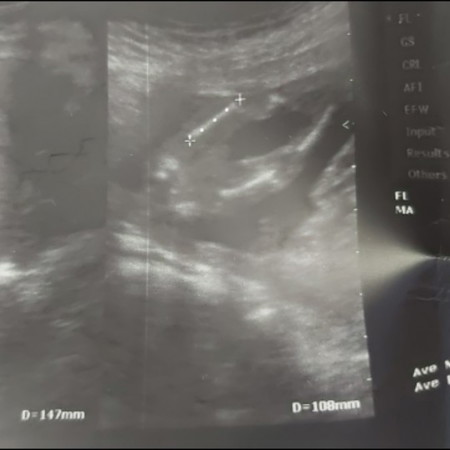

ซาวตอน 15 วีคชัวร์ไหมคะ

หมอบอกผู้ชาย 90% หมดสิทลุ้นลูกสาวแล้วใช่ไหมคะ มีแม่ๆคนไหนหมอดูผิดบ้าง เอาใบซาวมาแชร์หน่อยนะคะ (คนโตผู้ชาย 12 ขวบแล้วค่ะ)

ถ้าหมอฟันธงเมื่อไหร่ ก็หมดสิทธิ์แล้วจ้า เพราะแปลว่าจู๋โด่มาแล้ว หดหายไปไม่ได้จ้า